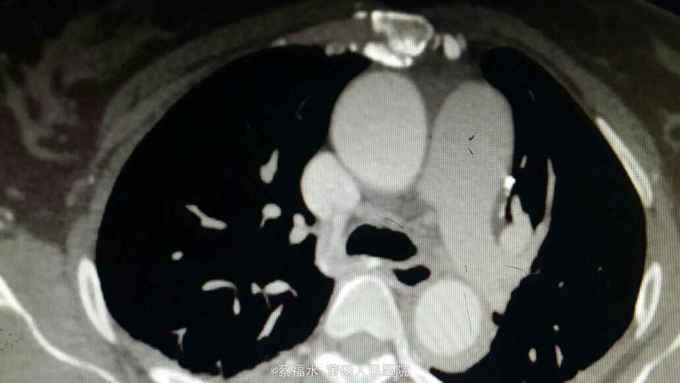

女性患者,56岁,以“上腹部、左腰部突发疼痛2小时”为主诉入院。入院查体:HR70次/分,BP220/105mmHg,双肺呼吸音清,未闻及干湿性啰音,心律齐,各瓣膜区未闻及杂音,腹平软上腹部压痛明显,无反跳痛,胆囊区无压痛,墨菲氏征阴性,肝脾肋下未及,左肾区叩痛可疑阳性,肠鸣音约5次/分。入院后查血淀粉酶正常,肌钙蛋白I阴性,心肌酶谱正常,心电图无心肌缺血改变,上腹部+胸部CT提示:右肾囊肿,余未见明显异常。予抑酸、维生素K3、曲马多等应用后,患者仍腹痛剧烈,性质同前,无明显缓解。予完善胸主动脉、腹主动脉、髂动脉CTA结果如下:

腹主动脉夹层动脉瘤 予控制血压、控制心率等治疗,患者腹痛较前缓解